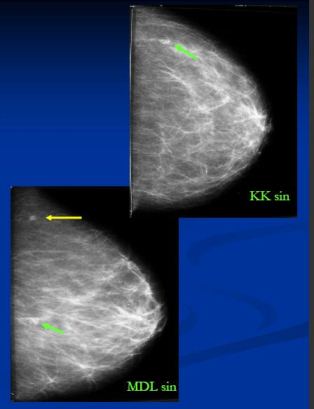

- Pouze v MDL projekci zachyceno 4mm ložisko v HQ – popsáno jako intramam.LU, nemá korelát v KK

- Ve FN HK před výkonem před lokalizací vodičem zhotoveny KK a bočná projekce sin

- Ložisko v KK projekci (CCB Hi: duktální Ca)